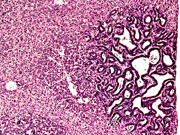

Ductular formation of hepatocytes in this 2-week old AL-TAg x AL-myc mouse has a predominantly centrilobular localization.

An altered hepatocyte focus is arising in an area of ductular formation in this 2-week old AL-TAg x AL-myc mouse.